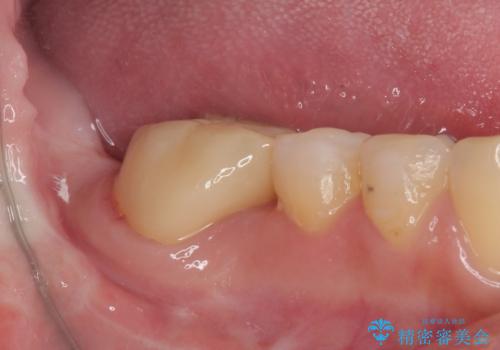

- 1本欠損したままの奥歯の治療を終えたいとのことで来院された患者様です。

奥歯が1本欠損した状態で矯正治療を行っていたそうですが、どのように治療を終了させるか未決のまま矯正装置を除去してしまい、暫く放置されている状態でした。

理想的には残っている歯のスペースを詰め、最後方にインプラントを埋入することが理想的ではありますが、矯正治療期間や費用の面から、前後に歯を大きくする補綴治療を行うことで対応することとなりました。